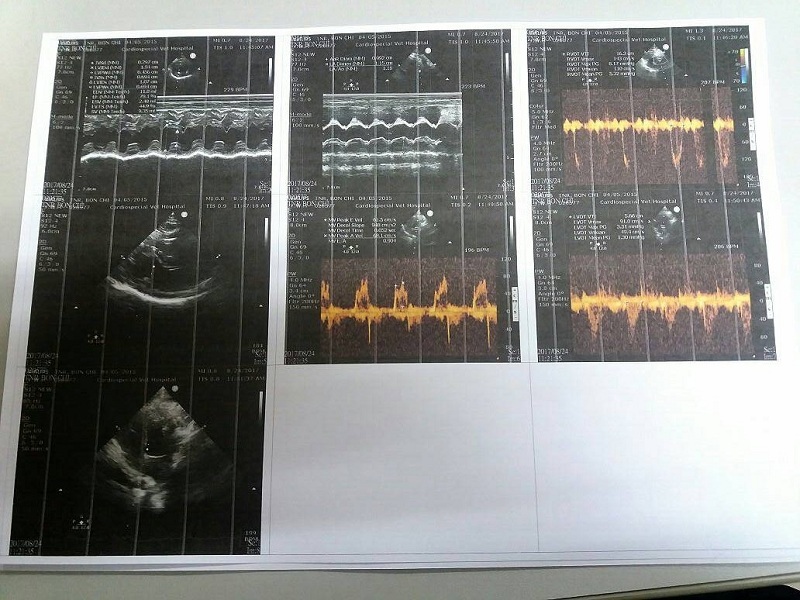

主題: 因心臟病回診超音波以及X光檢查的罔市 申請者姓名: 臺北市支持流浪貓絕育計劃協會 花色: 申請日期: 2017-09-13 14:27:21 申請者部落格: 申請者臉書網址: 所在縣市/合作醫院: 台北市/其他院所醫助專案(醫院請先MAIL溝通) 治療費用: 5500元 需求人數: 13人 已結案 (2024-06-01 13:22:36) 報名人員: 心桓 x2(已付款)、Moon x2(已付款)、Emily Yen(已付款)、Queenie Cheng(已付款)、Grace Tsao x2(已付款)、Jessica Hsu、王員外的爹(已付款)、nicole chen(已付款)、詹曉青(已付款)、洪凱威 x2(已付款)、 候補人員: 動物病情說明: 罔市由於疝氣以及先天的心臟疾病,從小十分瘦弱

每半年也需至心臟專科查看超音波並拍攝X光

於上半年的檢查結果下,罔市的心臟狀況趨向樂觀

原先希望經過半年後,罔市的心臟能夠恢復至可接受的大小及機能

但本次的回診結果下,罔市的心臟狀況不如預期…

以下為回診說明

8/24專心回診 罔市 5.25KG(半年前2/13,體重為4.9KG),體溫39.6(緊張)

【回診狀況】

罔市聽診,無心雜音

觸診淋巴正常無腫塊

但本次回診,半年前變小的左心室變大了(14.6-->19.2)

而原先大小未改變的右心室也變大了

整體心臟狀況退步,故罔市無法停藥